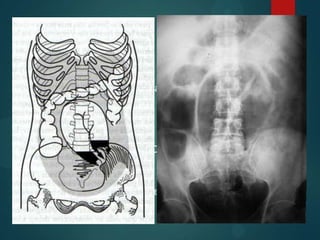

   La OI se caracteriza por dilatación de asa

intestinales proximales al punto de obstrucción.

Completa o incompleta

Intestino Delgado          Intestino Grueso

• Asas de ID dilatadas    • Se identifican

(>2.5-3 cm                haustras

), centrales            • Asas dilatadas

• Niveles hidroaéreos       mayor 9, 6, 12 cm y

en escalera               periféricas

• Ausencia de gas en      • No se observa aire

el colón.                 en el recto           Proyecciones

• Pilas de monedas        • Niveles hidroaereos

• Signo del "collar de    • Distensión Ciego      Diferencias

perlas"                 • Zonas más             en válvulas

anteriores

Bipedestación: múltiples          Decúbito supino: múltiples asas

niveles hidroaereos en escalera   de ID dilatadas, válvulas

y signo del collar de perlas.     conniventes prominentes

Radiología simple de abdomen  La OI se caracteriza por dilatación de asa intestinales proximales al punto de obstrucción. Completa o incompleta Intestino Delgado Intestino Grueso • Asas de ID dilatadas • Se identifican (>2.5-3 cm haustras ), centrales • Asas dilatadas • Niveles hidroaéreos mayor 9, 6, 12 cm y en escalera periféricas • Ausencia de gas en • No se observa aire el colón. en el recto Proyecciones • Pilas de monedas • Niveles hidroaereos • Signo del "collar de • Distensión Ciego Diferencias perlas" • Zonas más en válvulas anteriores

Bipedestación: múltiples Decúbito supino: múltiples asas niveles hidroaereos en escalera de ID dilatadas, válvulas y signo del collar de perlas. conniventes prominentes

• #13 Alto grado de obstrucción del intestino delgado. Radiografía simple de abdomen muestra múltiples niveles hidroaéreos (flechas), algunas de ellas con una anchura de más de 2,5 cm. Además, existe un diferencial de altura vertical de más de 2 cm entre correspondientes niveles hidroaéreos en el lazo intestinal mismo (en el círculo de área). Existe también la distensión del diámetro del intestino delgado a más de 2,5 cm y una pequeña proporción del intestino y coma diámetro superior a 0,5